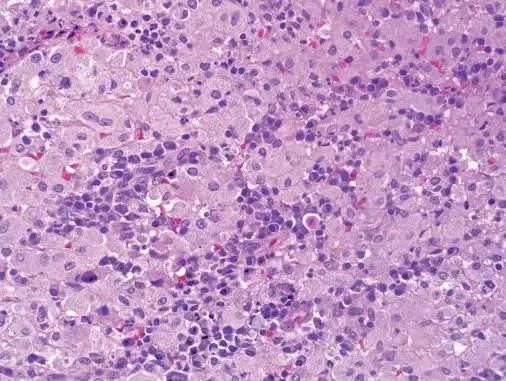

你知道吗?这种类型的肺结核,它不像那些一发病就大张旗鼓的家伙,它低调得很,但破坏力一点不小。它会让你的肺部出现一片片的阴影,就像是乌云密布的天空,让人心里直发毛。而且,它还特别喜欢在年轻人和免疫力低下的人身上“安家”,真是让人防不胜防。